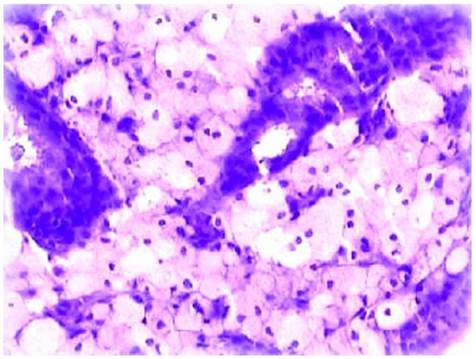

Figure 5

Disintegration of the endometrial glands accompanied by infiltration of abundant foam cells.

Microscopic examination: The glandular architecture of the endometrium was preserved, and the lining epithelial cells were focally crowded in considerable fields. The stroma was infiltrated by focal or sheets of foam cells admixed with lymphocytes, plasma cells and occasional neutrophils (Figure 5). These foam cells had light staining, comparatively small nuclei surrounded by abundant cytoplasm containing lipid vacuoles. Immunohistochemical stains demonstrated CD68 positivity in the foam cells, CD20 and CD3 were positive in the lymphocytes. The endometrial epithelium was not reactive to ER and PR. The pathological diagnosis rendered xanthogranulomatous endometritis.